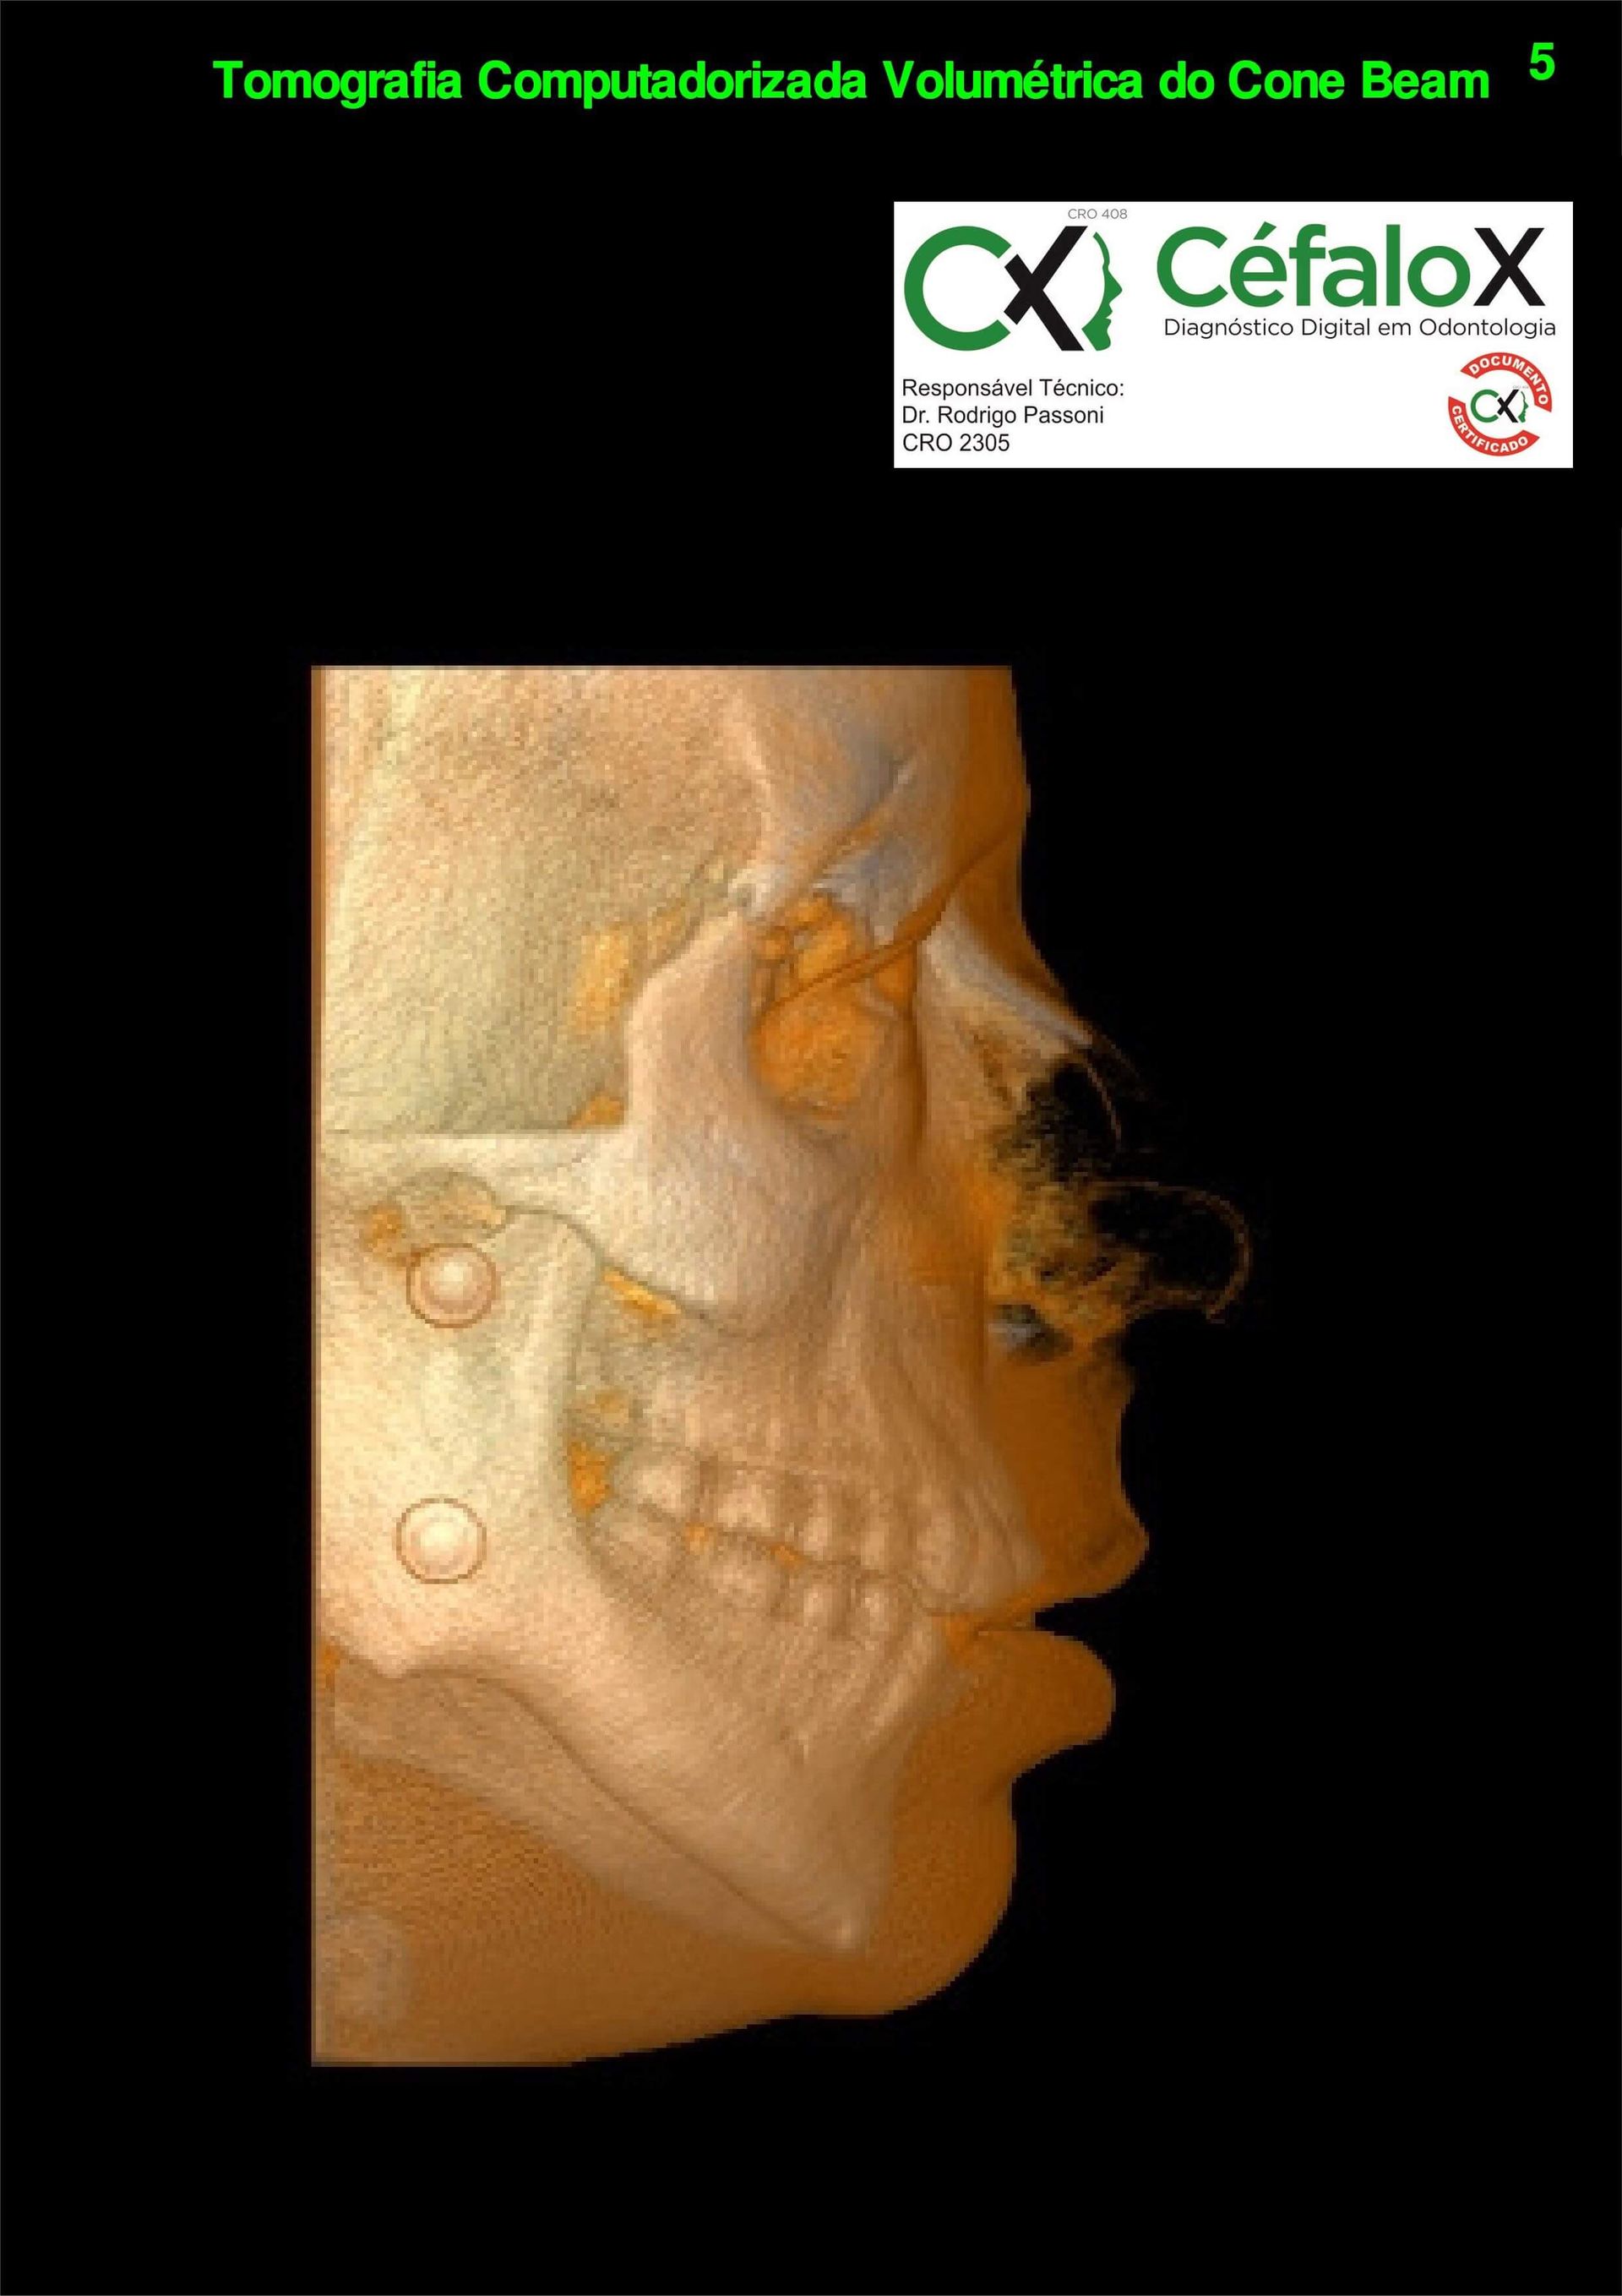

TC de face (do Hióide à Glabela), reconstrução 3D do tecido ósseo, radiografia panorâmica, telerradiografia lateral com traçado, cortes transversais e axial de maxila e mandíbula e arquivo DICOM- entregue em pasta de Pvc.

TC de face (do Hióide à Glabela), reconstrução 3D do tecido ósseo, radiografia panorâmica, telerradiografia lateral e frontal com traçado, cortes transversais e axial de maxila/mandíbula e arquivo DICOM – entregue em pasta de Pvc.

TC de face (do Hióide à Glabela), reconstruções 3D do tecido mole/ósseo/vias aéreas, radiografia panorâmica, telerradiografia lateral e frontal com traçado, cortes transversais e axial de maxila/mandíbula, ATM e arquivo DICOM – entregue em pasta e caixa de Pvc.